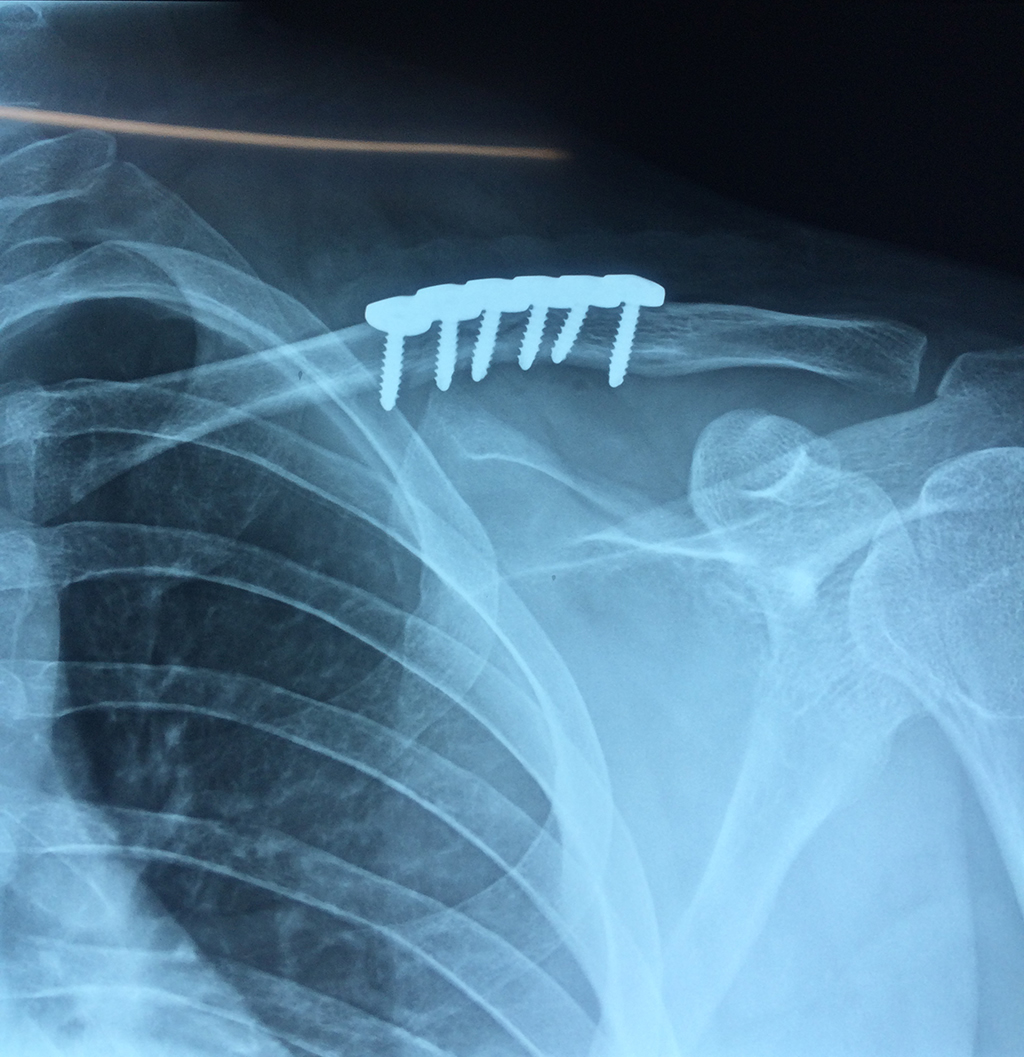

La clavícula es un hueso largo, con forma de "S" itálica, situado en la parte anterosuperior del tórax. Junto con la escápula forman la cintura escapular. Se puede palpar por toda su longitud y se extiende del esternón al acromion de la escápula, siguiendo una dirección oblicua lateral y posterior.

Se considera el único medio de unión entre el miembro superior y el tórax. A pesar de su aspecto, similar al de un hueso largo, posee una estructura semejante a la de un hueso plano, ya que carece de epífisis y de diáfisis, lo que la harían entrar dentro de la clasificación de hueso largo. Carece de un canal medular propiamente dicho.